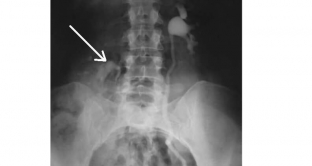

- екскреторна урографія – виконується у горизонтальному та вертикальному положенні, дозволяє визначити зміщення нирки за рахунок її відношення до хребців. Нормальна рухливість нирок становить висоту тіла максимум півтора хребця;